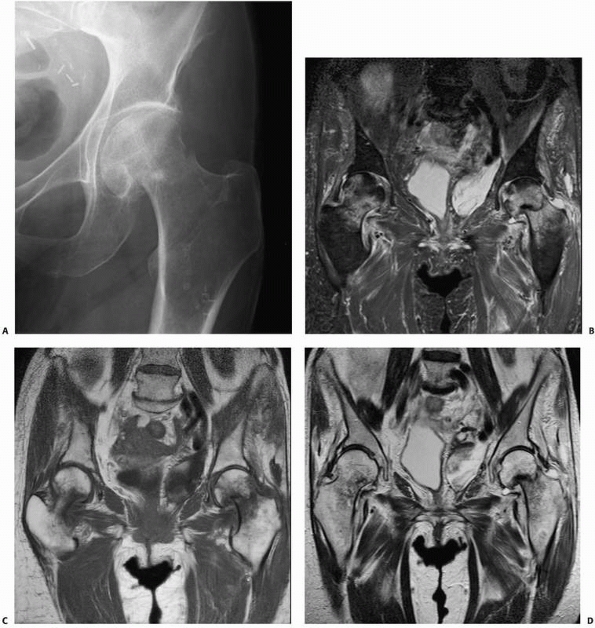

FIGURE 16-7 A.

Conventional plain anteroposterior radiograph of a patient’s hip demonstrates a femoral neck fracture. Although the fracture can be seen on routine radiographs, the patient was at risk for osteonecrosis because of corticosteroid use related to a kidney transplant. Some apparent changes are seen in the bone density of the femoral head. Magnetic resonance imaging of the pelvis confirms the presence of an acute left hip fracture and demonstrates that there was no osteonecrosis. Incidentally noted is a small developing fracture with surrounding stress reaction in the right femoral neck medially: (B) STIR, (C) T1-weighted, and (D) T2-weighted images. Higher-resolution images of the left hip fracture demonstrating mild impaction at the fracture site without significant angulation. (continues) |

![]() |